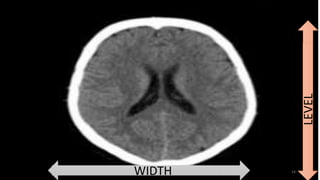

Brightness- window level Contrast- window width

14WIDTH

LEVEL